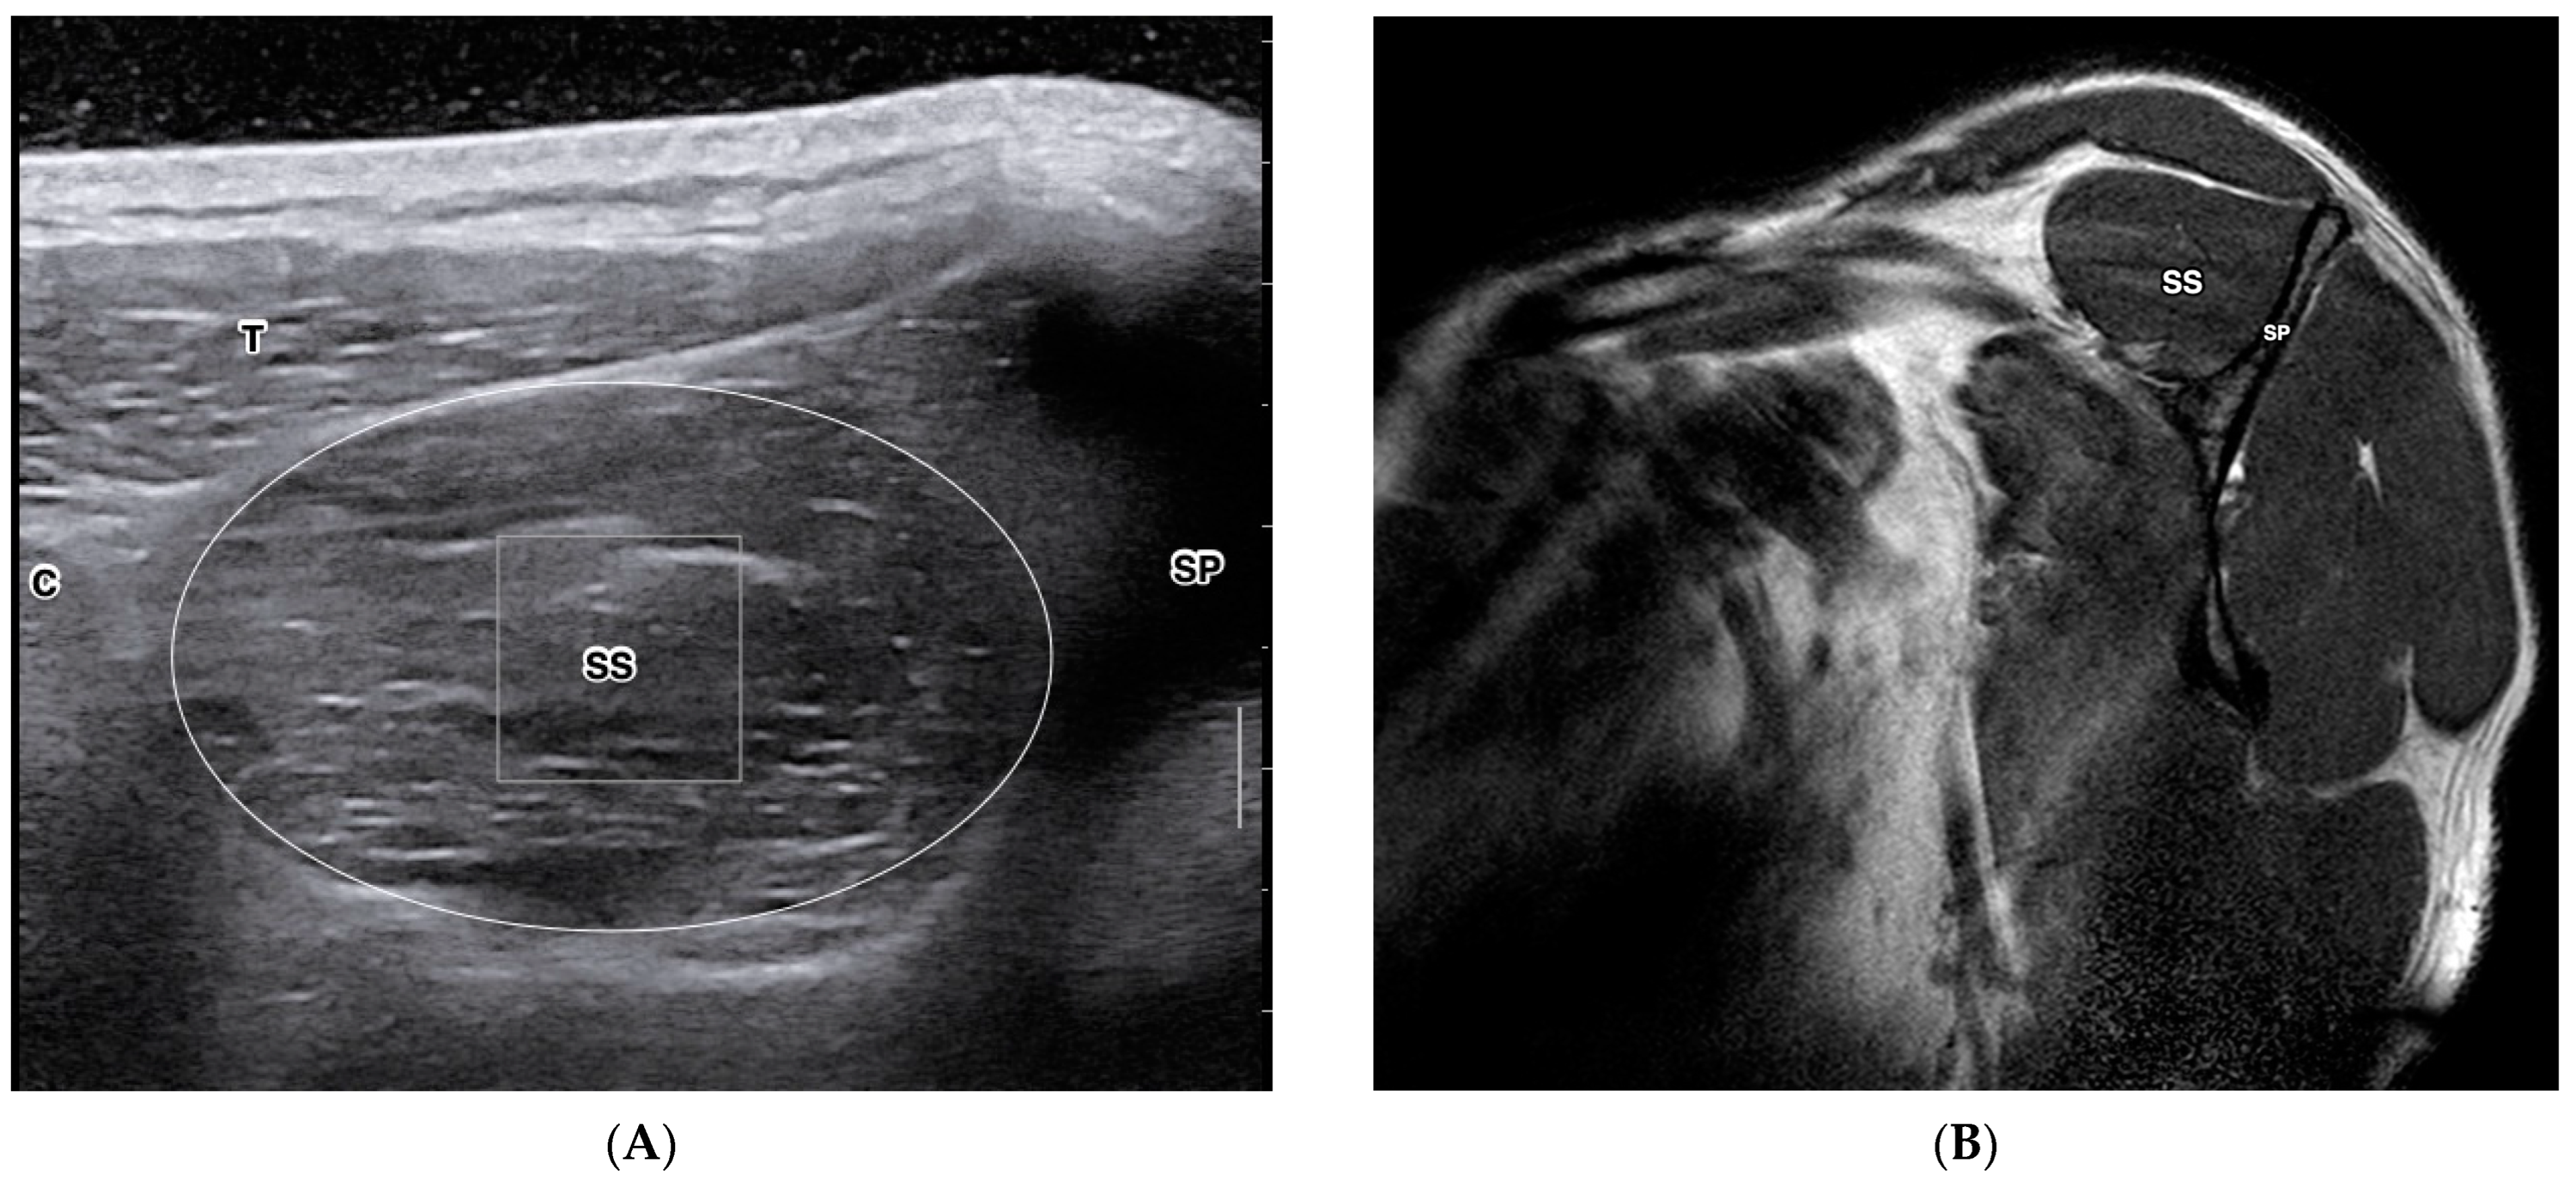

- Park, B.K.; Hong, S.H.; Jeong, W.K. Effectiveness of Ultrasound in Evaluation of Fatty Infiltration in Rotator Cuff Muscles. Clin. Orthop. Surg. 2020, 12, 76–85. [Google Scholar] [CrossRef] [PubMed]

- Watanabe, T.; Terabayashi, N.; Fukuoka, D.; Murakami, H.; Ito, H.; Matsuoka, T.; Seishima, M. A pilot study to assess Fatty infiltration of the supraspinatus in patients with rotator cuff tears: Comparison with magnetic resonance imaging. Ultrasound Med. Biol. 2015, 41, 1779–1783. [Google Scholar] [CrossRef]

- Seo, J.B.; Yoo, J.S.; Ryu, J.W. The accuracy of sonoelastography in fatty degeneration of the supraspinatus: A comparison of magnetic resonance imaging and conventional ultrasonography. J. Ultrasound 2014, 17, 279–285. [Google Scholar] [CrossRef] [PubMed]

- Wall, L.B.; Teefey, S.A.; Middleton, W.D.; Dahiya, N.; Steger-May, K.; Kim, H.M.; Wessell, D.; Yamaguchi, K. Diagnostic performance and reliability of ultrasonography for fatty degeneration of the rotator cuff muscles. J. Bone Jt. Surg. Am. 2012, 94, e83. [Google Scholar] [CrossRef]

- Khoury, V.; Cardinal, E.; Brassard, P. Atrophy and fatty infiltration of the supraspinatus muscle: Sonography versus MRI. AJR Am. J. Roentgenol. 2008, 190, 1105–1111. [Google Scholar] [CrossRef]